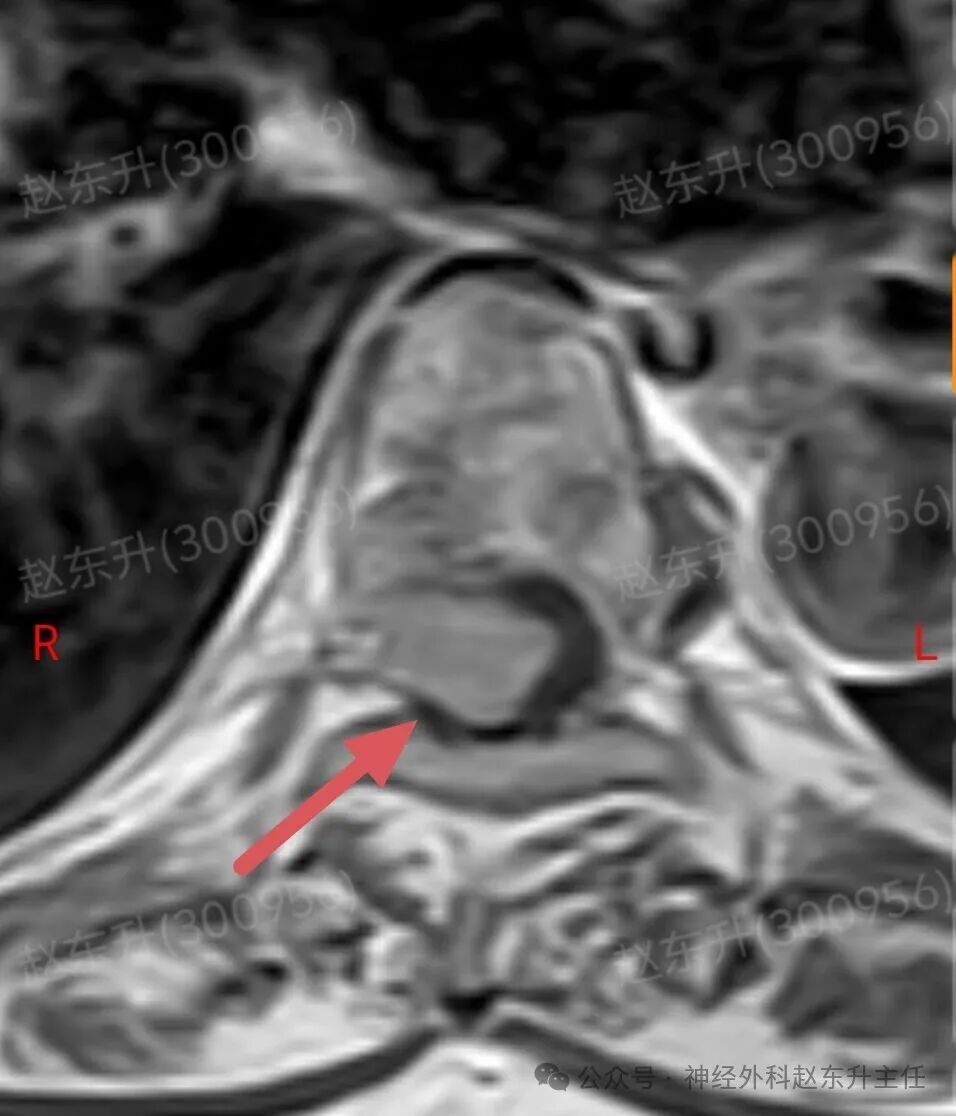

今天介绍一个58岁女性患者,因为腰部疼痛麻木伴双下肢麻木乏力半年入院的患者半年前开始出现下肢麻木乏力,但可独立行走。没有引起重视,逐渐症状加重,伴有腰部疼痛,夜间疼痛比较明显明显难以忍受,随后在当地医院查了ct和核磁共振发现椎管内一个巨大的肿瘤压迫脊髓。当地医院不敢手术,因为患者虽然疼痛麻木,疼痛评分有10分,但可以行走。随后他到西安市红会医院神经外科找到了赵东升主任,经过详细的术前评估和检查以后在全麻下显微镜下进行了肿瘤全切术后患者疼痛立即减轻,术后第2天开始做经颅磁刺激等神经康复治疗。术后一周就可以下地行走了,大小便也恢复了正常。患者感激到终于有人帮我解决了这个折磨他半年的一个疾病。

磁共振成像:是首选和确诊性检查。典型表现:T1加权像呈等或稍低信号,T2加权像呈等或稍高信号;增强扫描后呈现均匀、显著的强化,可见特征性的“硬膜尾征”(邻近硬脊膜线状强化)。